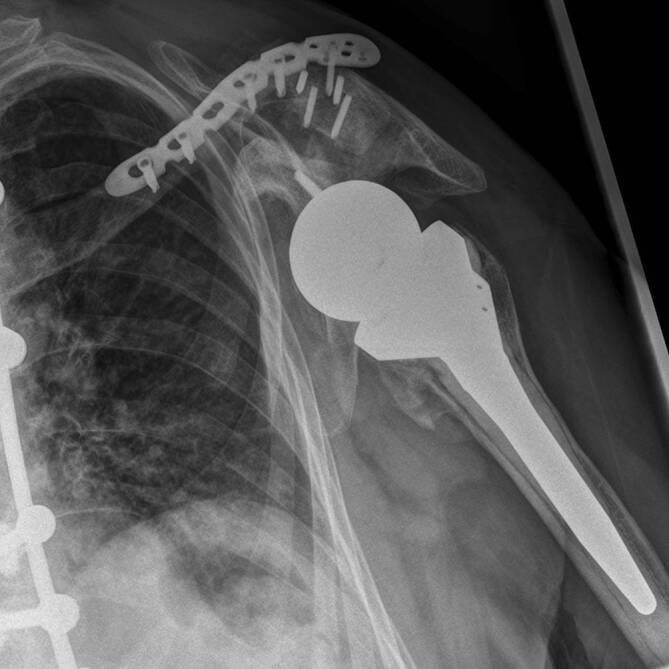

We present a rare case of clavicle fracture following reverse shoulder arthroplasty (RSA). This complication may be caused by the higher tension of the deltoid muscle after RSA, similarly to stress fractures of the acromion. Associated bone disease, i.e. osteoporosis, may contribute. In the few case reports available, the affected patients showed significant functional impairments. In the current case, the fracture was addressed with plate fixation. Despite good intraoperative results, osteosynthesis failure with secondary dislocation of the fracture occurred.

我们报告一例罕见的反肩关节置换术(RSA)后锁骨骨折病例。这种并发症可能是由于RSA后三角肌张力增加所致,类似于肩峰应力性骨折。相关的骨病,即骨质疏松症,可能起了一定作用。在现有的少数病例报告中,受影响的患者出现了明显的功能障碍。在本例中,骨折采用钢板固定治疗。尽管术中效果良好,但仍发生了骨合成失败及骨折继发性脱位。